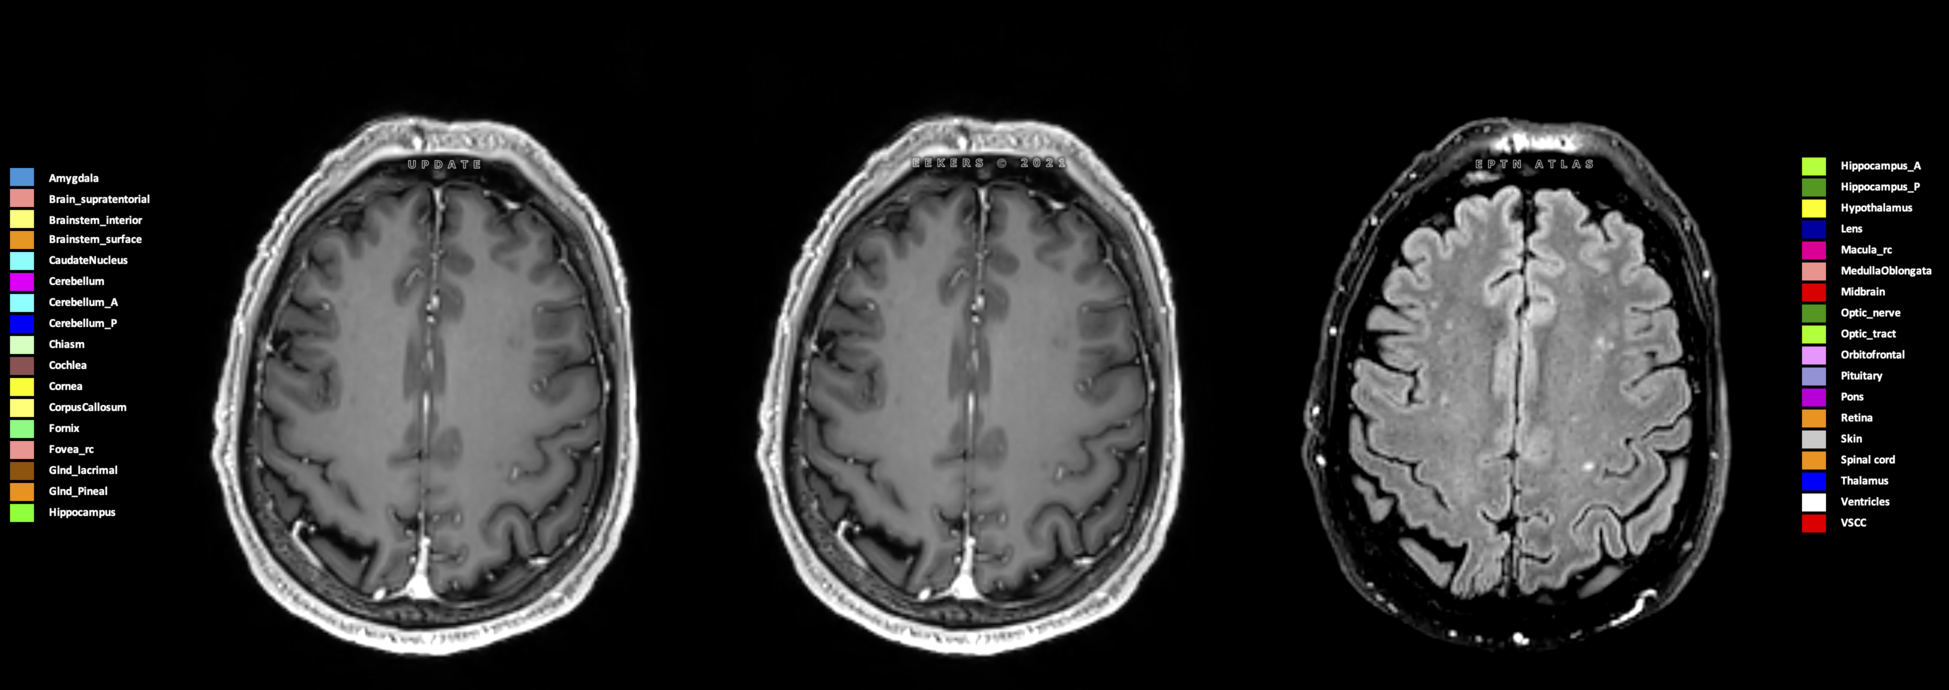

Eekers et al. have published an international neurological atlas for contouring of organs at risk in consensus with the European Particle Therapy Network (EPTN) in 2018 and an update in 2021. The purpose of this consensus atlas is to decrease inter- and intra-observer variability in delineating OARs relevant for neuro-oncology.

Included are all OARs known to be relevant for radiation-induced toxicity in neuro-oncology: brain, brainstem (midbrain, pons, medulla oblongata), chiasm, cerebellum (anterior & posterior), cochlea, cornea, hippocampus (anterior & posterior), hypothalamus, lens, lacrimal gland, optic nerve, pituitary, skin, and vestibular & semicircular canals. To further facilitate research on cognition, vision and radiological changes after irradiation of the brain, potential clinically-relevant OARs are included: amygdala, caudate nucleus, cerebellum (anterior & posterior), corpus callosum, fornix, macula, optic tract, orbitofrontal cortex, periventricular space (PVS), pineal gland, and thalamus.

Three-dimensional delineation of the 25 consensus OARs for neuro-oncology are shown on CT (WW/WL 120/40, 3000/600), 3T MR images, (T1Gd, T2FLAIR 1mm) and 7T MR (MP2RAGE 0.7 mm). All are presented in transversal, sagittal and coronal view.